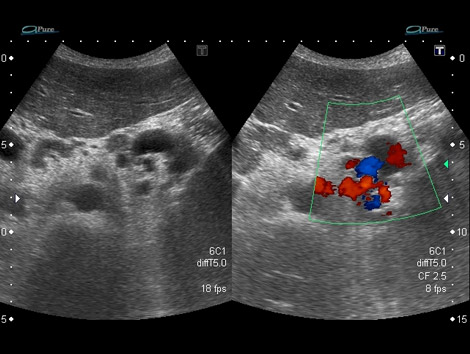

6.1. Hipertensión portal